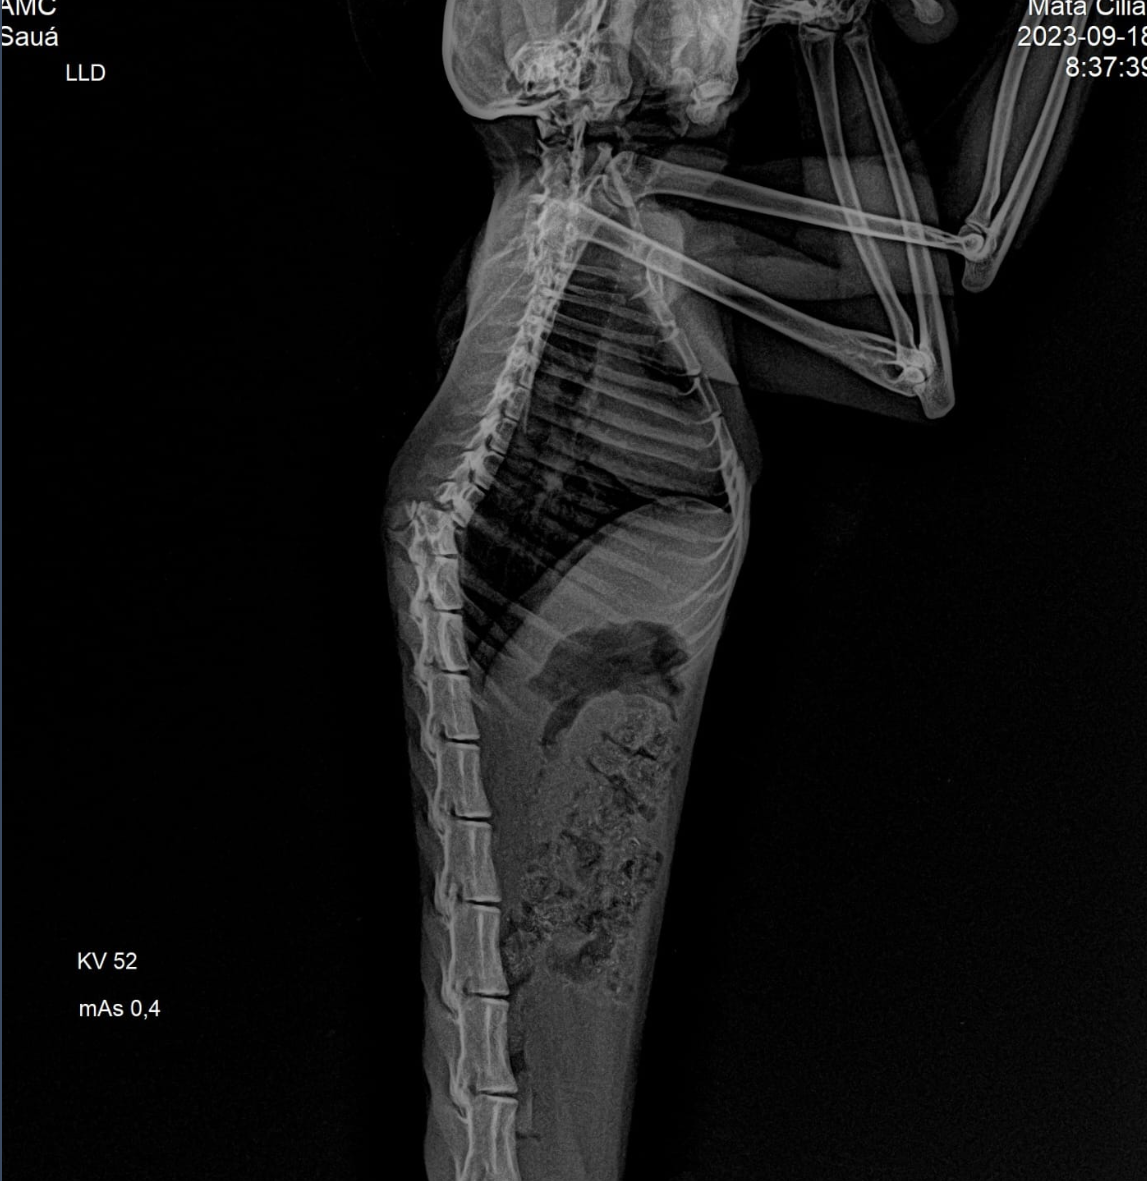

"No exame de raio-x, identificamos uma fratura na coluna torácica, e ele não apresentava reflexos de dor profunda ou superficial, tornando uma cirurgia inviável. Seu prognóstico era extremamente sombrio, já que ele não conseguia mover nenhum dos membros pélvicos (traseiros) e só se arrastava. Portanto, optamos pela eutanásia", explicou Paula Campanholi, médica veterinária da Mata Ciliar.